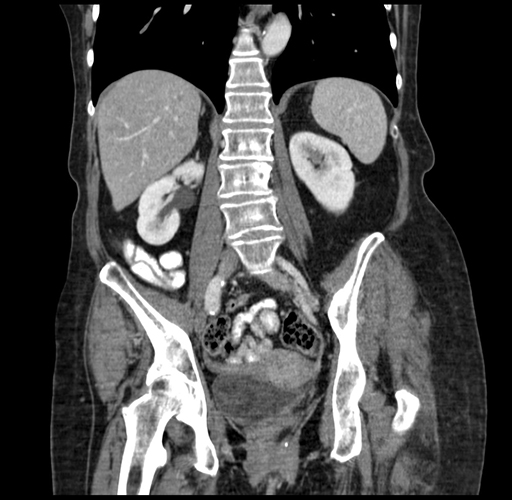

Pre-Chemo: Coronal Venous

Coronal Venous